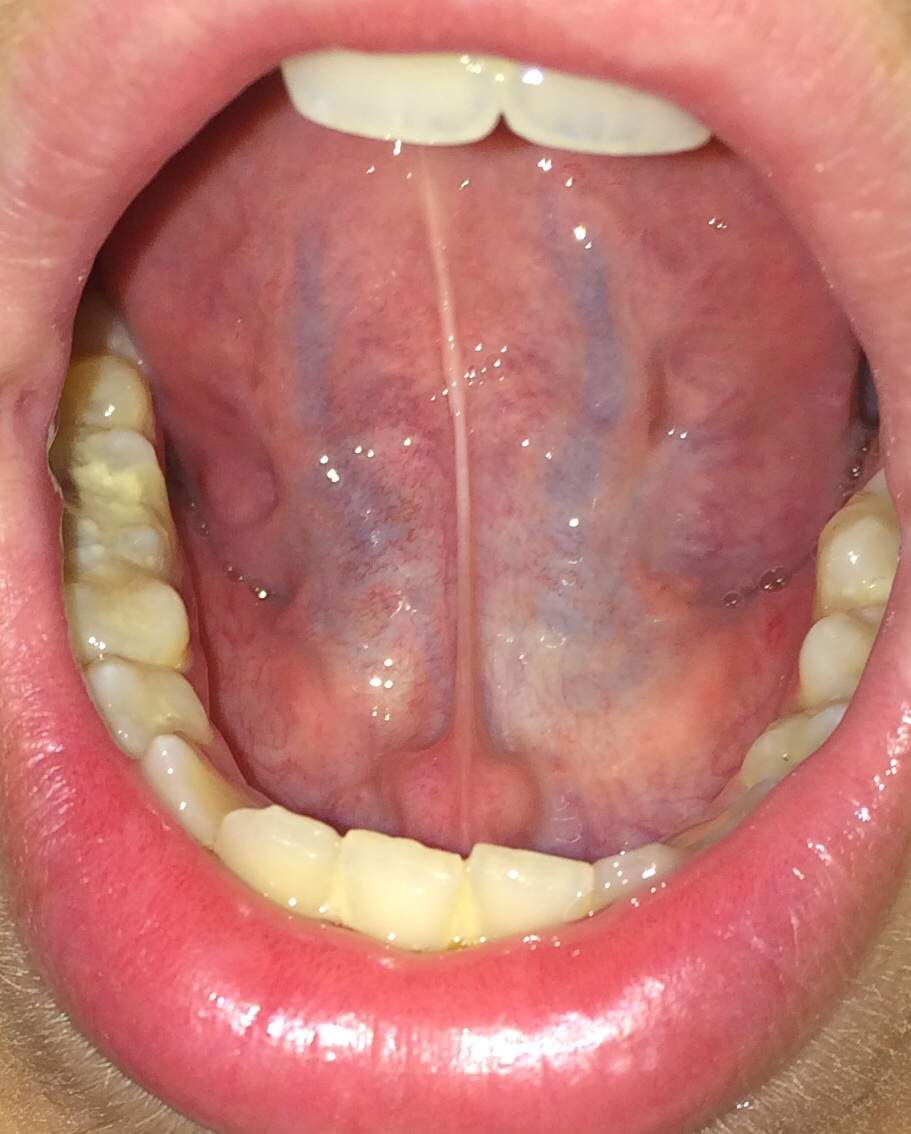

Was sind das für blaue Streifen unter meiner Zunge? (Gesundheit, Medizin, Mund)